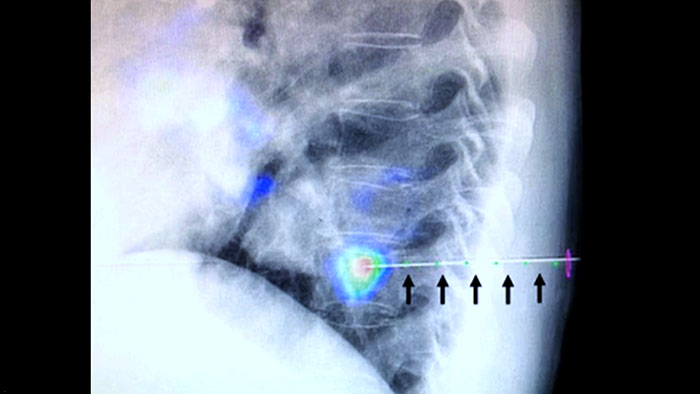

O XperGuide fornece uma orientação por imagem ao vivo altamente precisa de cada agulha para um posicionamento direcionado sobrepondo trajetórias pré-planejadas ao diagnóstico por imagem fluoroscópico.3

A heterogeneidade da lesão e a falta de conspicuidade limitam a qualidade das amostras, além da viabilidade das biópsias quando realizadas durante o ultrassom ou a tomografia convencional. Com a crescente adoção de programas de exames preventivos do pulmão, os cânceres de pulmão iniciais que se manifestam como pequenos nódulos têm sido detectados com maior frequência do que nunca. Nódulos ≤ 10 mm foram observados em 14,5% de uma

população examinada.1-2 Nossa tecnologia de navegação de agulha com CBCT aumenta a precisão e permite enfocar lesões menores (< = 1 cm) ou heterogêneas com maior exatidão e menos reposicionamento da agulha, com uma dose menor que a de uma tomografia convencional.1-2